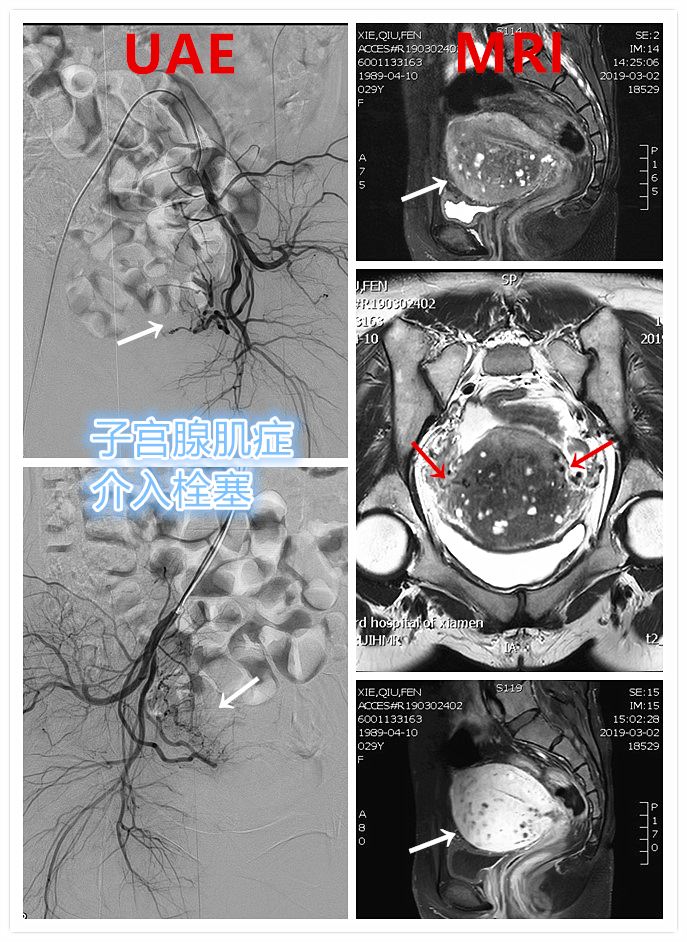

例1

青年女性患者,痛经近10年,近5年痛经明显加重。确诊为子宫腺肌症(弥漫型),经放置曼月乐、注射亮丙瑞林等妇科保守治疗,症状缓解不理想,痛经进行性加重,严重困扰工作与生活。

- 行子宫腺肌症介入栓塞治疗

- 插管至右侧髂内动脉造影,显示右侧子宫动脉

- 插管至右侧子宫动脉,显示子宫右侧病灶情况

- 插管至左侧子宫动脉,显示子宫左侧病灶情况

- 术前MRI显示子宫明显增大,病灶主要位于子宫前壁

术前MRI显示子宫明显增大,病灶主要位于子宫前壁

术后3个月复查MRI显示子宫明显缩小,前壁病灶萎缩坏死